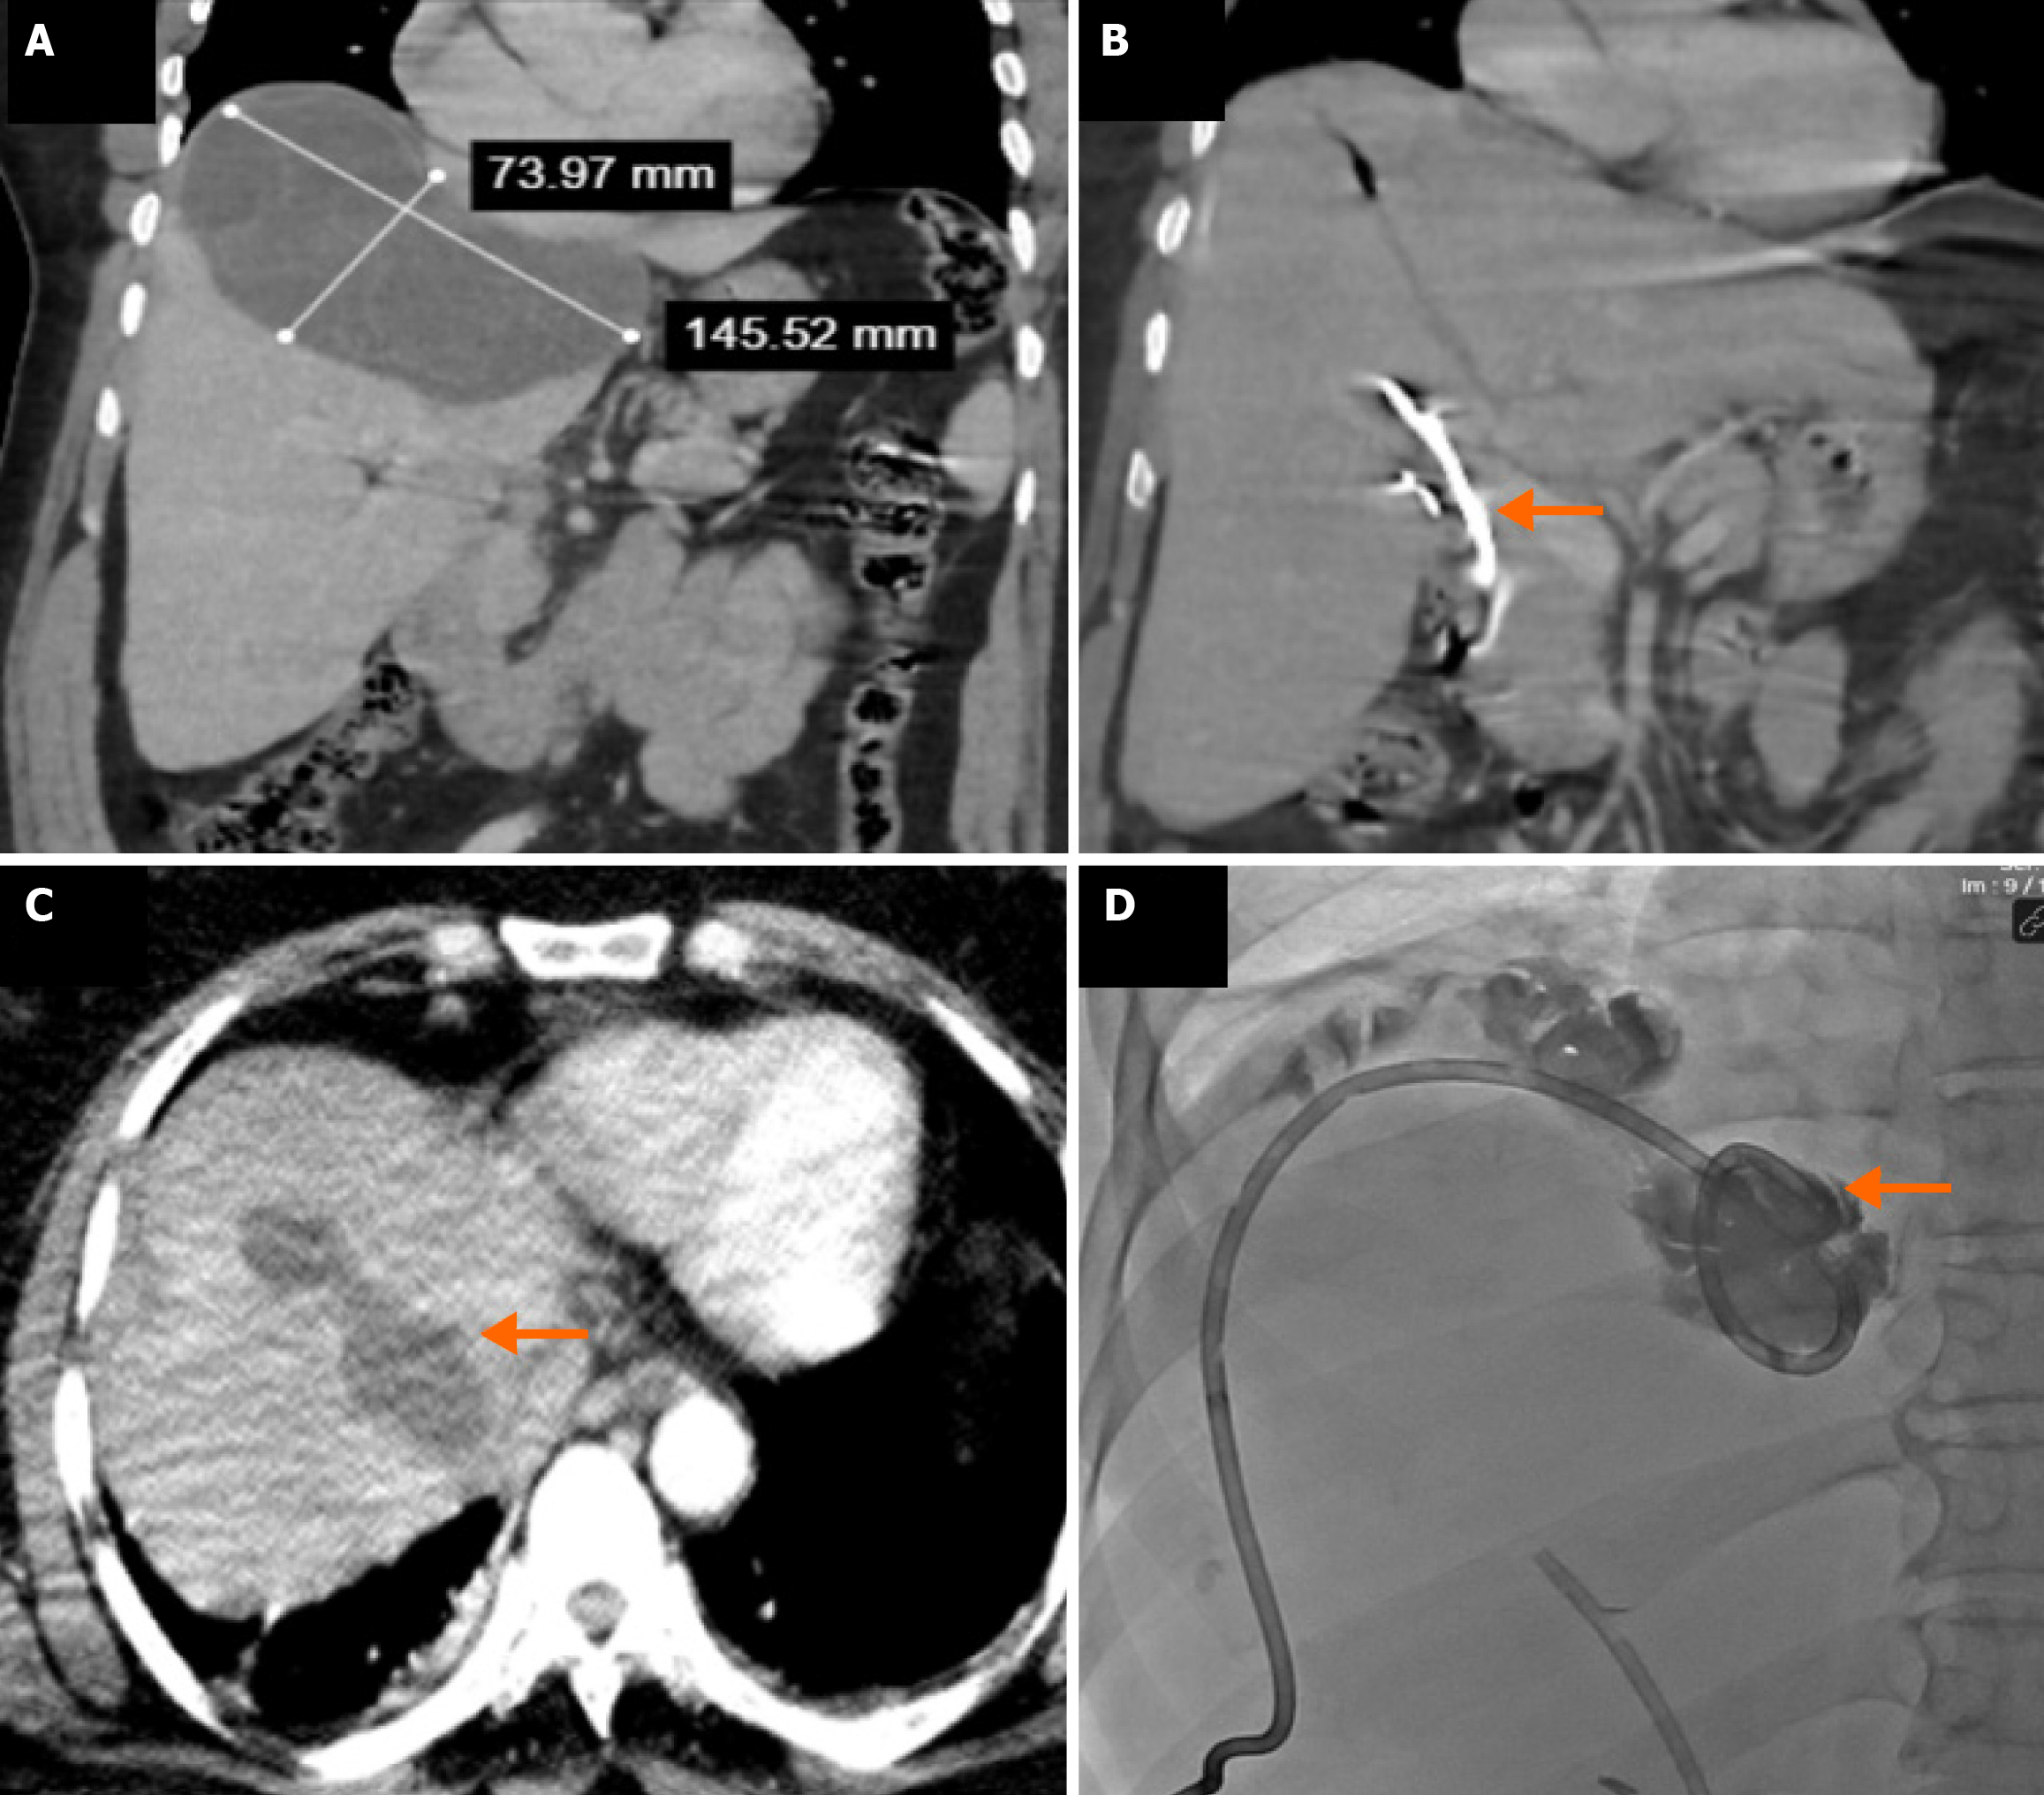

As shown in Table 5, during follow-up after treatment, the mean final cyst volume was significantly lower in the surgical group compared to the percutaneous group (46.9 ± 38.8 mL vs 63.3 ± 55.6 mL, respectively; P = 0.025), and the final volume reduction rate was statistically higher in the surgical group (88.9% vs 83.1%; P = 0.005) (Figure 6). The mean duration of follow-up imaging was significantly different between the groups, being 12.0 months (range: 3-60 months) in the surgical group and 18.6 months (range: 8-60 months) in the percutaneous group (P < 0.001). Hospital stay and catheter removal time were also significantly longer in the surgical group than in the percutaneous group (7.3 ± 6.2 days vs 3.1 ± 2.3 days, respectively; P < 0.001, and 6.6 ± 5.3 days vs 5.5 ± 6.4 days, respectively; P = 0.014). Among uncomplicated cases, the mean procedure duration was significantly longer in the surgical group [81.3 ± 27.6 minutes (range: 40-180 minutes) vs 40.4 ± 6.2 minutes (range: 30-60 minutes); P < 0.001]. In the surgical group, operation duration was considerably longer in patients who experienced complications (Table 5). Recurrence or recollection defined as symptomatic fluid accumulation in the cavity reaching initial volume levels was observed in 17 patients (2.3%) in the surgical group and 16 patients (6.3%) in the percutaneous group (P = 0.002). These patients underwent drainage or secondary surgery (Figure 7).